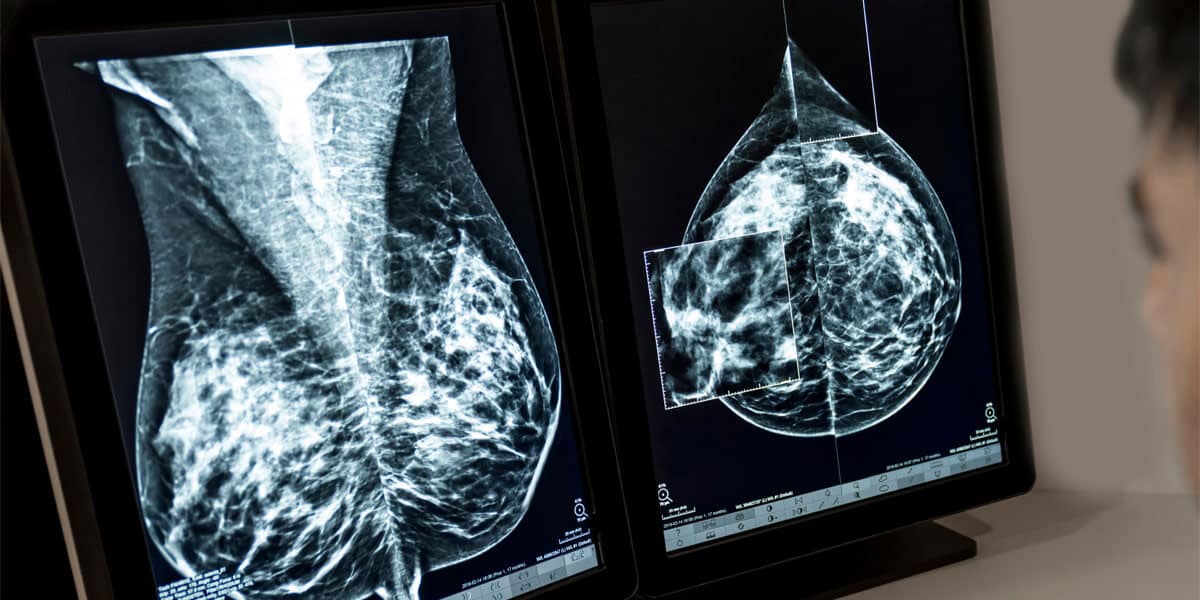

Axia Women’s Health has introduced MammoScreen, an advanced AI tool designed to support radiologists in detecting breast cancer earlier and more accurately.

“It’s a technology we wanted to bring to our patients. MammoScreen works as a second set of eyes with the radiologist. The radiologist reads the mammogram, and then MammoScreen reviews it—green is good, yellow is intermediate, and red is highly suspicious.”

“The AI system has been trained on millions of mammograms, both 2D and 3D, to identify subtle abnormalities. It assigns each image a score from 1 to 10 to indicate the level of suspicion.” He added “I personally had a patient that was diagnosed sooner so I was wondering if that could be very well responsible for that earlier detection.”